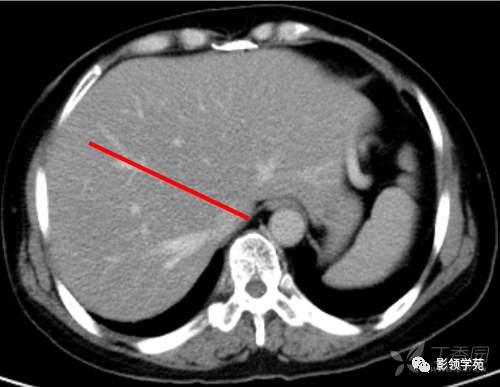

肝脏八段分法的影像学解剖示意图

第二肝门下方层面CT横断面

CT:首先找出肝脏的三大静脉:肝中静脉,肝左静脉,肝右静脉,找出门静脉及其分叉部位。门静脉分叉部位可以区分上段和下段,即肝S8/S5,S7/S6,门静脉分叉以上为S8、S7;肝右静脉和肝中静脉之间是右前叶,肝右静脉以后是右后叶

一般规律,从CT上看,最先看到的是S8然后是S2、3,肝左外叶以肝裂为界,左内叶为肝裂和肝中静脉之间的区域,胆囊往下的层次是S5,最后的层面一般是S6,下腔静脉和门静脉夹着的是尾状叶,即S1。